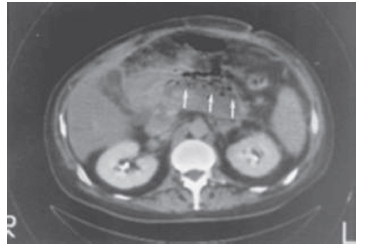

Paciente internado no CTI com pancreatite aguda apresenta piora do quadro e necessita de instalação de aminas vasopressoras. Solicitada uma tomografia abdominal do paciente, a imagem é a seguinte:

A conduta a ser seguida é:

fazer drenagem cirúrgica ou radiológica.